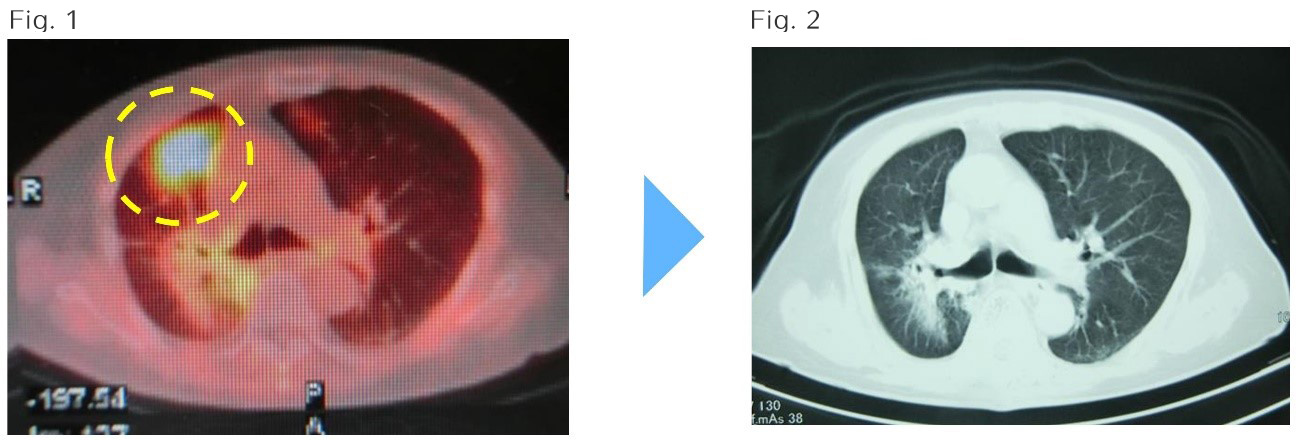

Does SBRT Revolutionize Metastatic NSCLC?

Does SBRT Revolutionize Metastatic NSCLC? www.medscape.com

sbrt lung cancer stereotactic radiation therapy radiotherapy does body seals decade role early its treatment immunotherapy revolutionize metastatic proviso screening